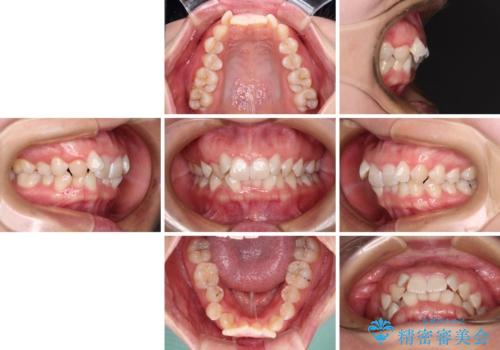

- 上下前歯のデコボコを気にして来院された患者様です。

口元の突出感はあまりなかったものの、デコボコを非抜歯で改善すると出っ歯になる可能性があるため、上下左右の第一小臼歯4本を抜歯し、ワイヤー装置にて矯正治療を行うこととしました。